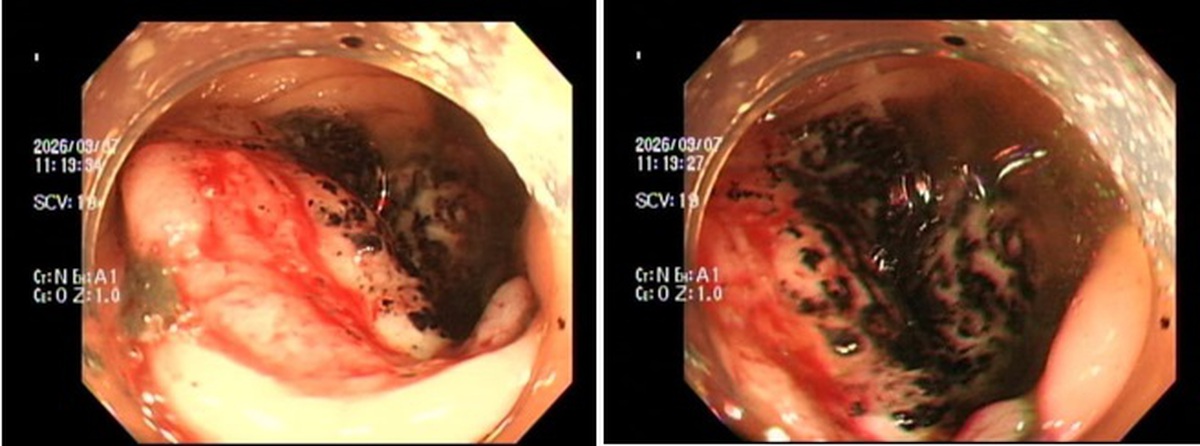

Ung thư đại trực tràng là bệnh ung thư bắt đầu từ ruột già (đại tràng) hoặc trực tràng Soha+1. Bệnh có thể diễn biến âm thầm trong giai đoạn đầu và thường không có triệu chứng rõ ràng. Khi bệnh tiến triển, các triệu chứng có thể bao gồm thay đổi thói quen đi tiêu, máu trong phân, đau bụng, sụt cân không rõ nguyên nhân Soha+1. Nếu có bất kỳ triệu chứng nào kể trên, người bệnh nên đi khám bác sĩ để được chẩn đoán và điều trị kịp thời.